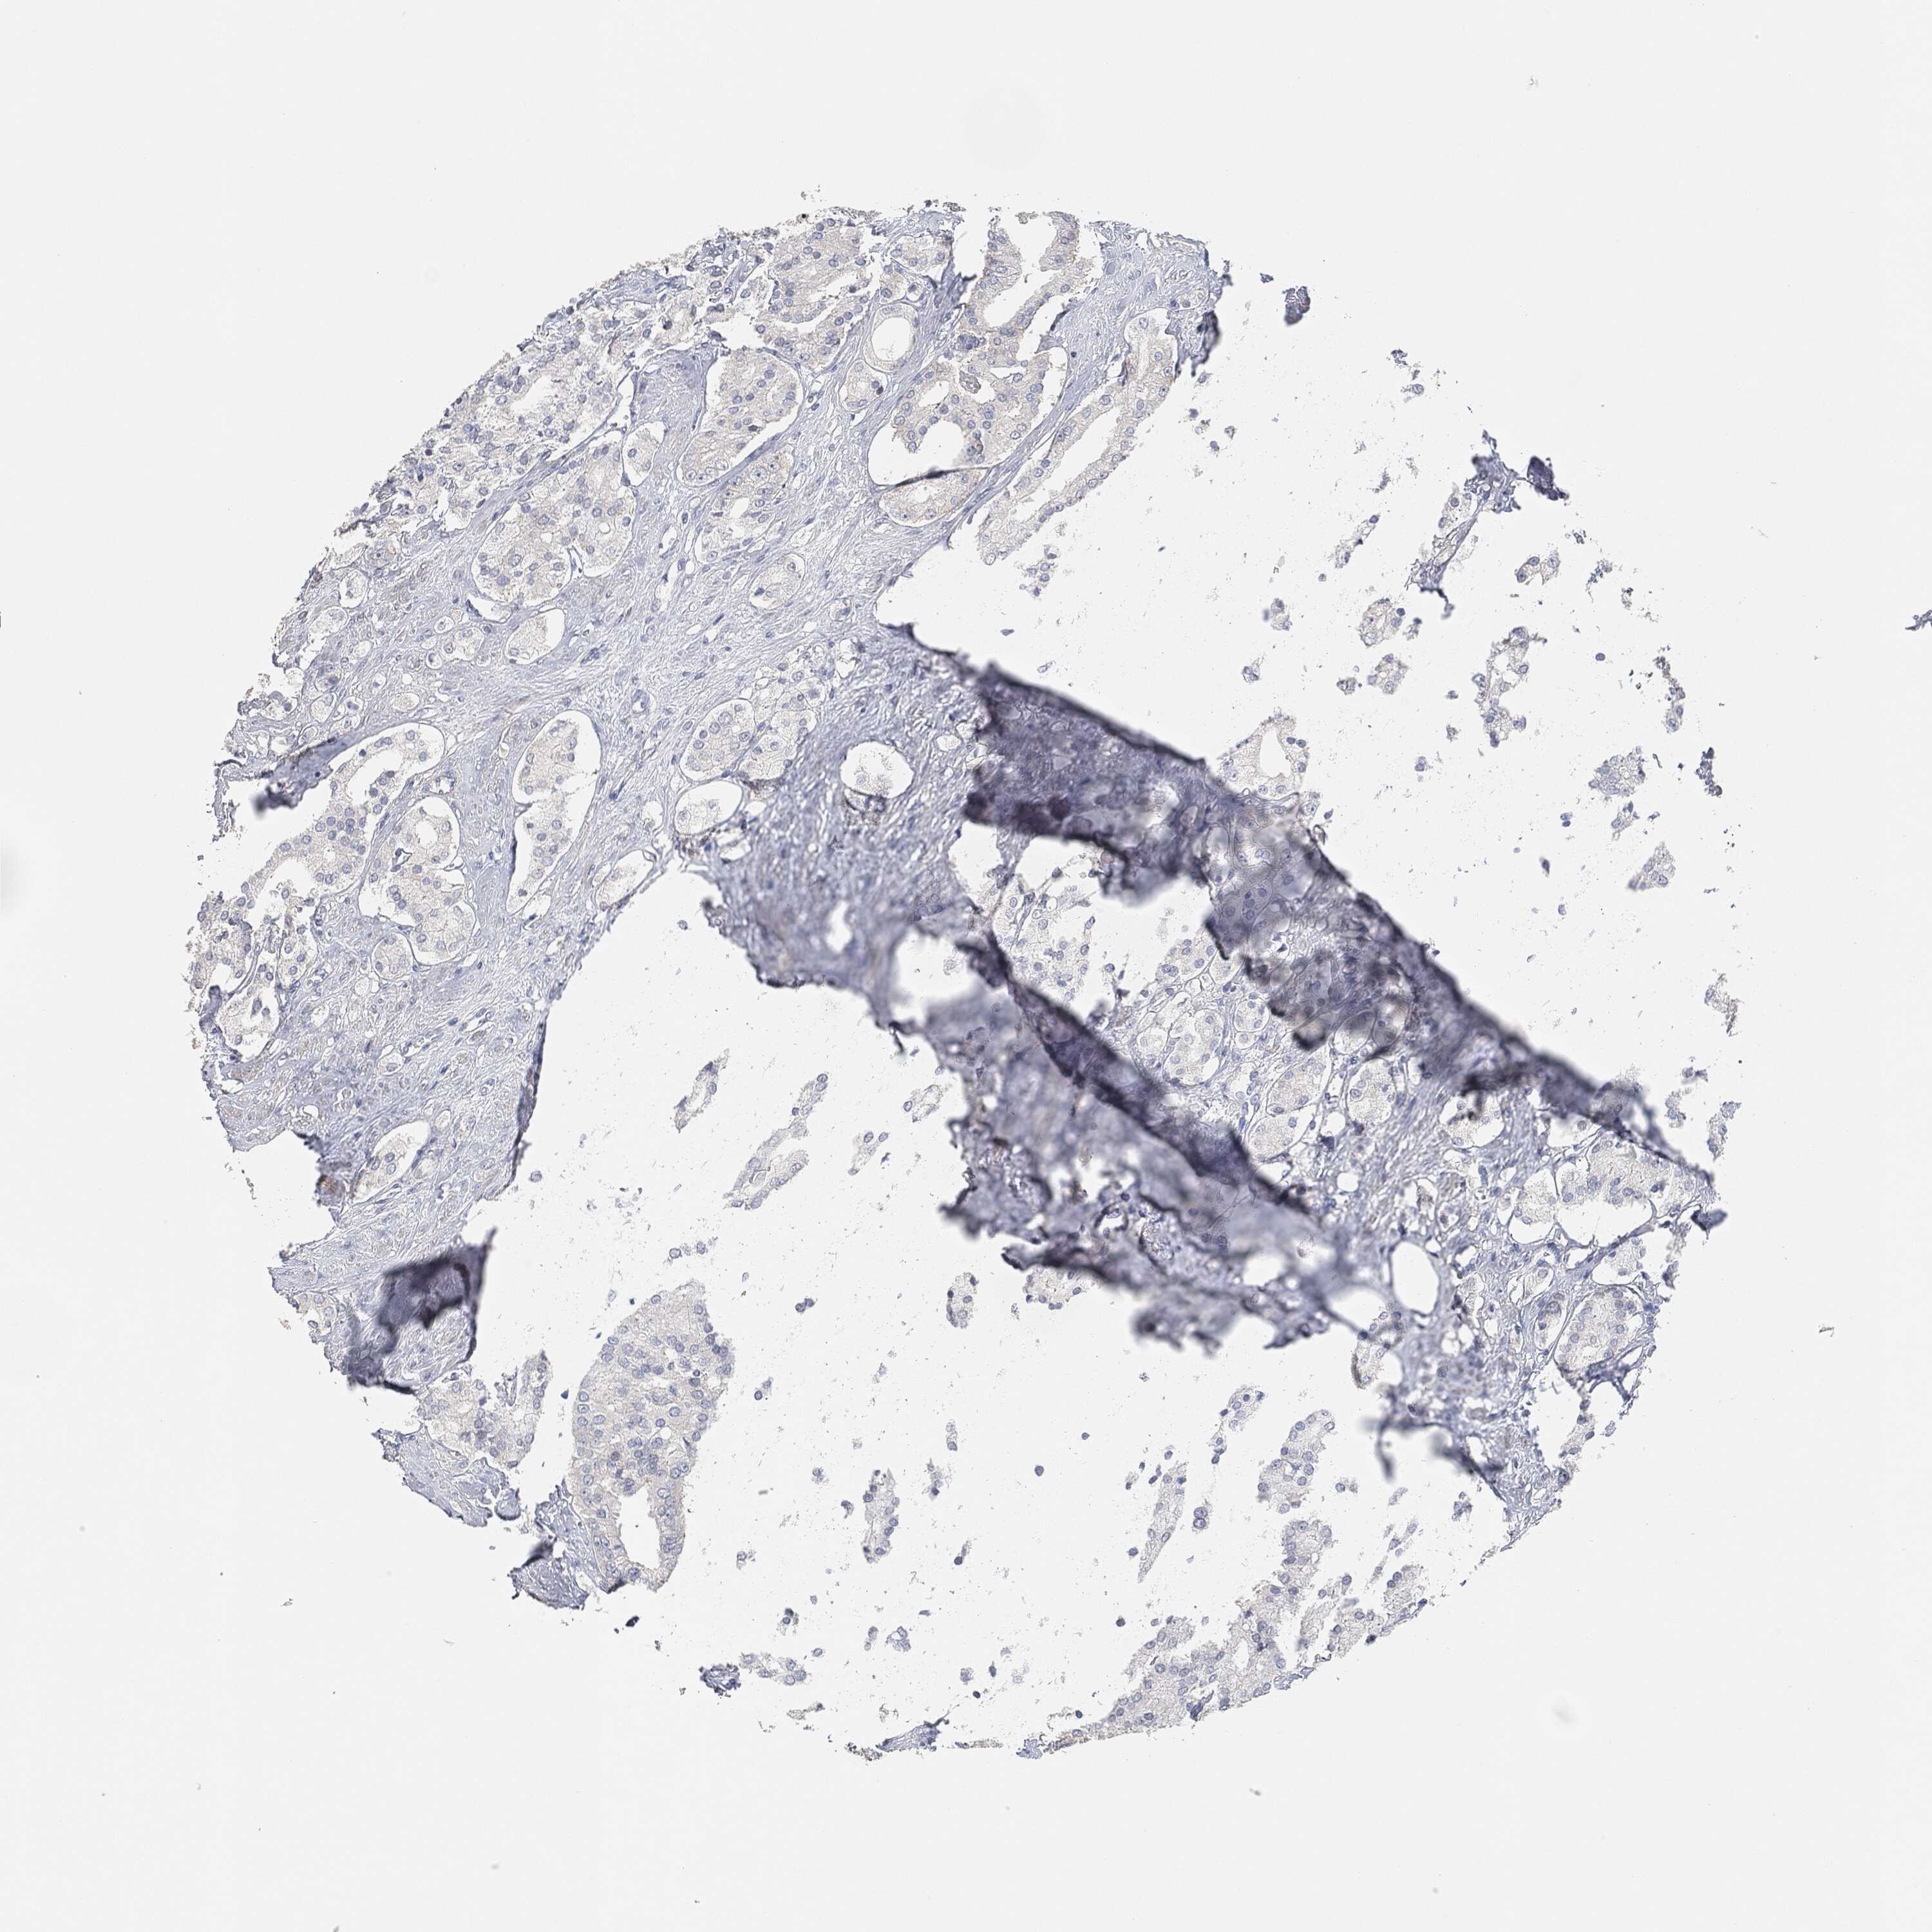

PROSTATE CANCER - Protein expressioni

A mouse-over function shows sample information and annotation data. Click on an image to view it in a full screen mode. Samples can be filtered based on level of antibody staining by selecting one or several of the following categories: high, medium, low and not detected. The assay and annotation is described here.

Note that samples used for immunohistochemistry by the Human Protein Atlas do not correspond to samples in the TCGA dataset.

Antibody stainingi

Antibody staining in the annotated cell types in the current human tissue is reported as not detected, low, medium, or high, based on conventional immunohistochemistry profiling in selected tissues. This score is based on the combination of the staining intensity and fraction of stained cells.

Each image is clickable and will lead to virtual microscopy that enables deeper exploration of all samples and also displays staining intensity scores, fraction scores and subcellular localization as well as patient and tissue information for each sample.

Adenocarcinoma, Medium grade

Adenocarcinoma, Low grade

Adenocarcinoma, High grade

Adenocarcinoma, NOS